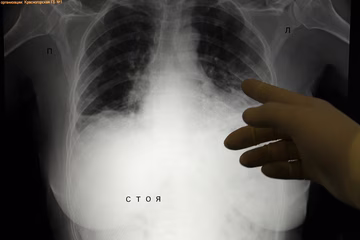

Kovid pluća s vakcinom i bez primljene vakcine FOTO

Pluća momka iz Kruševca - nisu ga rešetali meci nego korona